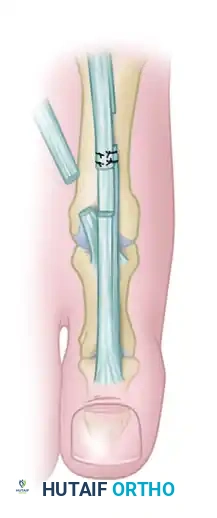

- If neutral position is attained: Maintain the IP joint in a straight position using two longitudinal transarticular Kirschner wires (K-wires) or a single obliquely placed wire.

- If neutral position cannot be attained: Proceed to an IP joint arthrodesis. Resect the articular cartilage and enough subchondral bone from both the proximal and distal phalanges to allow the joint to sit flush in a neutral position.

- Pinning Technique: Drive the K-wires retrograde through the distal phalanx so they emerge 2 to 3 mm plantar to the nail bed. Then, drive them proximally across the IP joint into the subchondral bone of the proximal phalanx.

Note: Occasionally, the K-wires must cross the first MTP joint for added stability, though a properly applied bulky forefoot dressing usually holds the MTP joint in the correct position without transarticular MTP pinning.

5. Correction of the Second Toe

Return to the first intermetatarsal space incision to manage the second toe MTP joint. Lengthen the EDL, tenotomize the EDB, and perform a dorsal capsulotomy and collateral ligament release at the second MTP joint, mirroring the steps performed on the hallux.